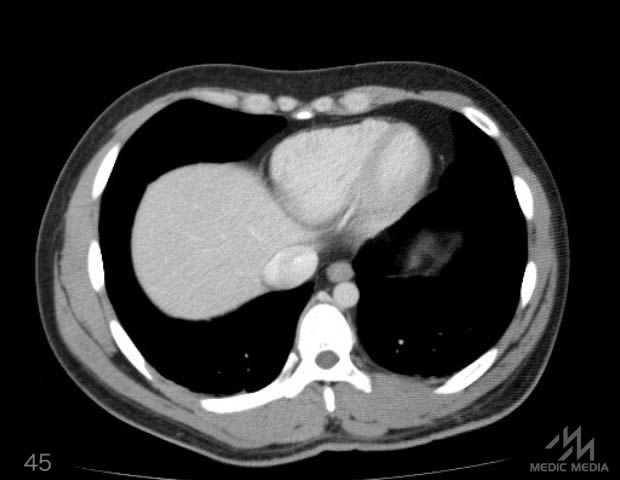

造影CT

消化器

肝区域